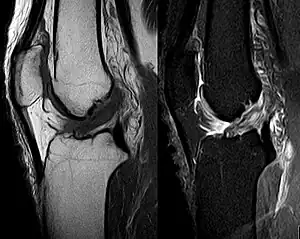

The unhappy triad, also known as a blown knee among other names, is an injury to the anterior cruciate ligament, medial collateral ligament, and meniscus. Analysis during the 1990s indicated that this 'classic' O'Donoghue triad is actually an unusual clinical entity among athletes with knee injuries. Some authors mistakenly believe that in this type of injury, "combined anterior cruciate and medial collateral ligament (ACL- MCL) disruptions that were incurred during athletic endeavors" always present with concomitant medial meniscus injury. However, the 1990 analysis showed that lateral meniscus tears are more common than medial meniscus tears in conjunction with sprains of the ACL.[1]

Injury

An anterior cruciate ligament injury results from excess tension on the ligament. This can come from a sudden stop or twisting motion of the knee. A few initial symptoms include swelling, knee instability, and pain. A popping sound or sensation may or may not be heard when the ACL first tears. A following symptom usually includes the feeling of the knee "giving out". Tearing of the ACL is the most significant injury because it leaves the knee unstable, which also causes the knee to lose its normal function.

Injury

The tear of meniscus is among the most common knee injuries. It is usually caused by torsional stress; twisting or turning of the knee too quickly with the foot planted on the ground while the knee is flexed. The feeling of a "pop" in the knee is usually felt when the meniscus is torn. Athletes, particularly those who participate in contact sports, are at a greater risk for meniscal tears. Sports-related meniscal tears often occur with other knee injuries, such as an anterior cruciate ligament tear.

A torn meniscus is commonly referred to as torn cartilage in the knee. Menisci tear in different ways and are noted by how they look, as well as where the tear occurs in the meniscus. Two types of tears include minor, which includes stiffness and swelling within two to three days but usually goes away in two to three weeks. Then there is severe, which without treatment, a piece of meniscus may come loose and drift into the joint space. Tears include longitudinal, parrot-beak, flap, bucket handle, and mixed/complex.